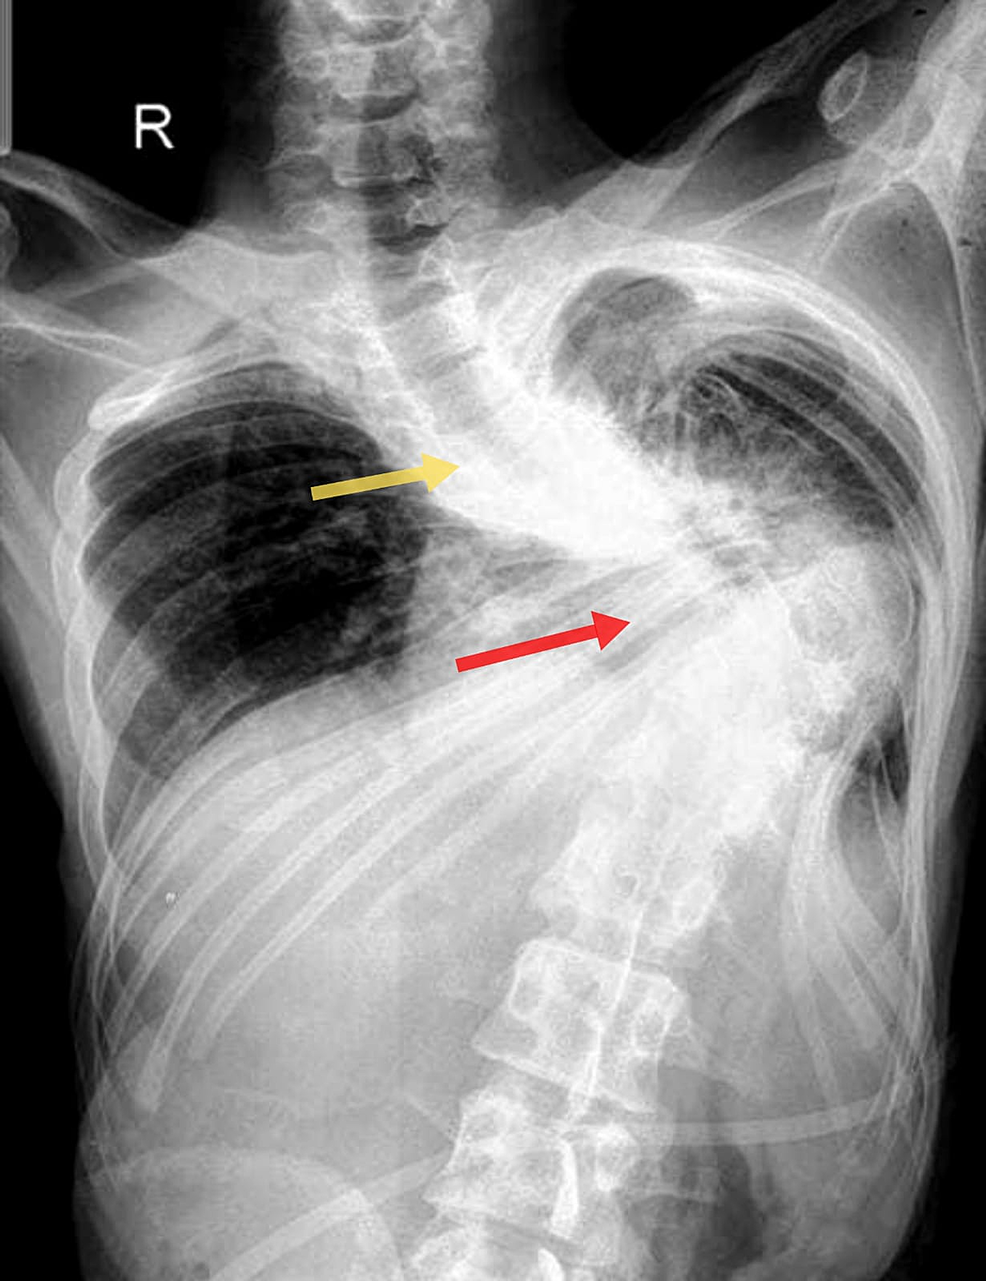

Figure 1 Pneumothorax with tracheal shift to right Tracheal Deviation Asthma The trachea deviates away from tension pneumothorax and large pleural effusions. The trachea deviates towards lobar collapse and pneumonectomy. Symptoms are variable (often worse at night, first thing in the morning, and upon. It is a symptom rather than a distinct diagnosis. The thorax should be examined for chest deformity or kyphosis and the movements should be. And evidence of. Tracheal Deviation Asthma.